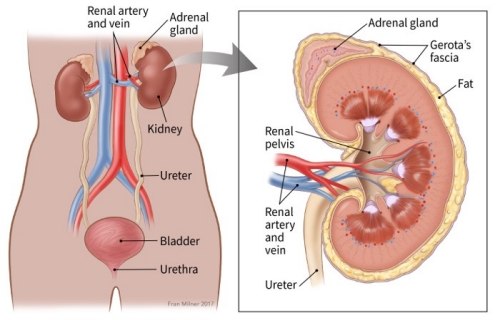

هر انسان دارای دو کلیه است که بزرگی هر یک به اندازه یک مشت است و هر کدام در یک طرف ستون فقرات در پایینترین سطح قفسه سینه قرار دارد. هر کلیه حدود یک میلیون واحد عملکردی به نام نفرون دارد. نفرون از واحد تصفیه کنندهی مویرگی به نام گلومرول تشکیل میشود که به توبول (لوله) متصل میشود. خون پس از ورود به گلومرول تصفیه میشود و مایع باقیمانده از توبول عبور میکند. در توبول آب و مواد شیمیایی بر حسب نیاز بدن به این مایع تصفیه شده اضافه یا از آن گرفته میشود و در نهایت فراوردهای به نام ادرار به دست میآید که باید از بدن دفع شود.

عملکرد اصلی کلیه دفع مواد زائد و مایعات اضافی از بدن است که از راه ادرار از بدن خارج میشوند. تولید ادرار مراحل بسیار پیچیدهی دفع و بازجذب دارد. این فرایند برای حفظ تعادل پایدار بین مواد شیمیایی بدن ضروری است. تنظیم حیاتی پتاسیم، مواد اسیدی و نمک بدن بر عهده کلیهها است. کلیهها همچنین هورمونها و ویتامینهایی را تولید میکنند که بر عملکرد دیگر اندامها اثر میگذارد. برای مثال یکی از هورمونهای تولید شده توسط کلیهها تولید گلبول قرمز را تحریک میکند. به علاوه کلیه هورمونهای دیگری ترشح میکند که یکی از آنها فشار خون را تنظیم میکند و بقیه نیز متابولیسم کلسیم را کنترل میکنند.

هر انسان دارای دو کلیه است که بزرگی هر یک به اندازه یک مشت است و هر کدام در یک طرف ستون فقرات در پایینترین سطح قفسه سینه قرار دارد. هر کلیه حدود یک میلیون واحد عملکردی به نام نفرون دارد. نفرون از واحد تصفیه کنندهی مویرگی به نام گلومرول تشکیل میشود که به توبول (لوله) متصل میشود. خون پس از ورود به گلومرول تصفیه میشود و مایع باقیمانده از توبول عبور میکند. در توبول آب و مواد شیمیایی بر حسب نیاز بدن به این مایع تصفیه شده اضافه یا از آن گرفته میشود و در نهایت فراوردهای به نام ادرار به دست میآید که باید از بدن دفع شود.

عملکرد اصلی کلیه دفع مواد زائد و مایعات اضافی از بدن است که از راه ادرار از بدن خارج میشوند. تولید ادرار مراحل بسیار پیچیدهی دفع و بازجذب دارد. این فرایند برای حفظ تعادل پایدار بین مواد شیمیایی بدن ضروری است. تنظیم حیاتی پتاسیم، مواد اسیدی و نمک بدن بر عهده کلیهها است. کلیهها همچنین هورمونها و ویتامینهایی را تولید میکنند که بر عملکرد دیگر اندامها اثر میگذارد. برای مثال یکی از هورمونهای تولید شده توسط کلیهها تولید گلبول قرمز را تحریک میکند. به علاوه کلیه هورمونهای دیگری ترشح میکند که یکی از آنها فشار خون را تنظیم میکند و بقیه نیز متابولیسم کلسیم را کنترل میکنند.